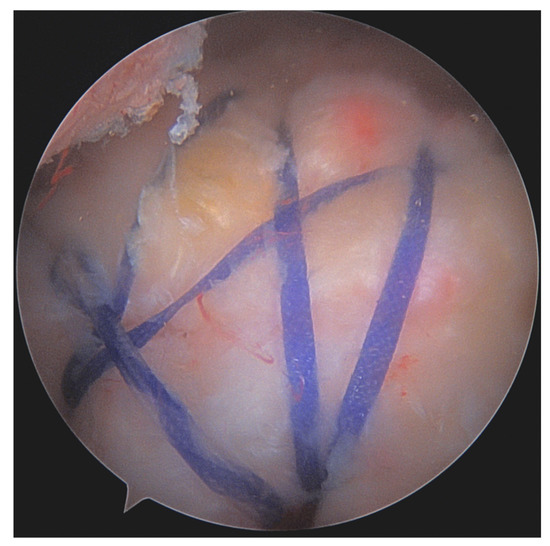

- Burkhart, S.S.; Athanasiou, K.; Wirth, M.A. Margin convergence: A method of reducing strain in massive rotator cuff tears. Arthrosc. J. Arthrosc. Relat. Surg. 1996, 12, 335–338. [Google Scholar] [CrossRef] [PubMed]

- Burkhart, S.S. The principle of margin convergence in rotator cuff repair as a means of strain reduction at the tear margin. Ann. Biomed. Eng. 2004, 32, 166–170. [Google Scholar] [CrossRef]

- Burkhart, S.S.; Danaceau, S.M.; Pearce, C.E. Arthroscopic rotator cuff repair: Analysis of results by tear size and by repair technique-margin convergence versus direct tendon-to-bone repair. Arthroscopy 2001, 17, 905–912. [Google Scholar] [CrossRef]

- Kim, K.C.; Shin, H.D.; Cha, S.M.; Kim, J.H. Repair Integrity and Functional Outcomes for Arthroscopic Margin Convergence of Rotator Cuff Tears. J. Bone Jt. Surg. 2013, 95, 536–541. [Google Scholar] [CrossRef]